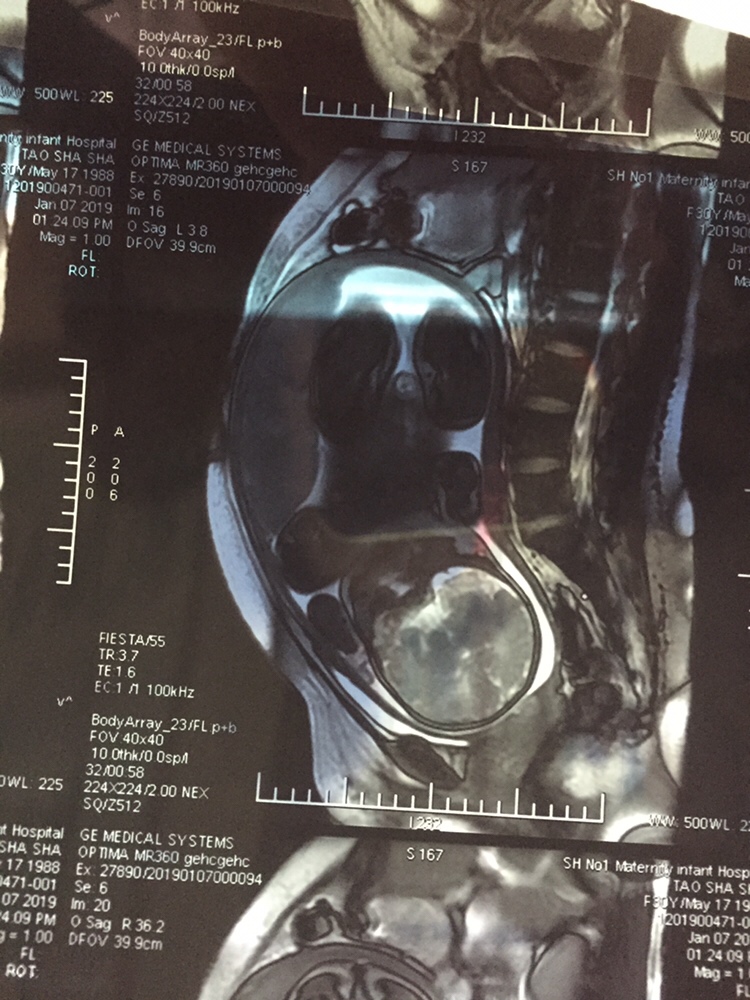

孕17周+0天

核磁共振对宝宝没有影响的吗

桃子[帖主]:没有辐射的,就是噪音非常大,胎动不安,很多孕妇做的

看了半天 没有看到孩子在哪里 哪里是头哪里是脚

团团思绮女王轻奢店(套现软件):下面是头

桃子[帖主]:为了排除胎盘植入的,不是必须做的

能拍核磁共振???

桃子[帖主]:排除胎盘植入的,因为有内膜炎和粘连,不是必须要做的

恭喜,是男宝宝吧

桃子[帖主]:好像是吧